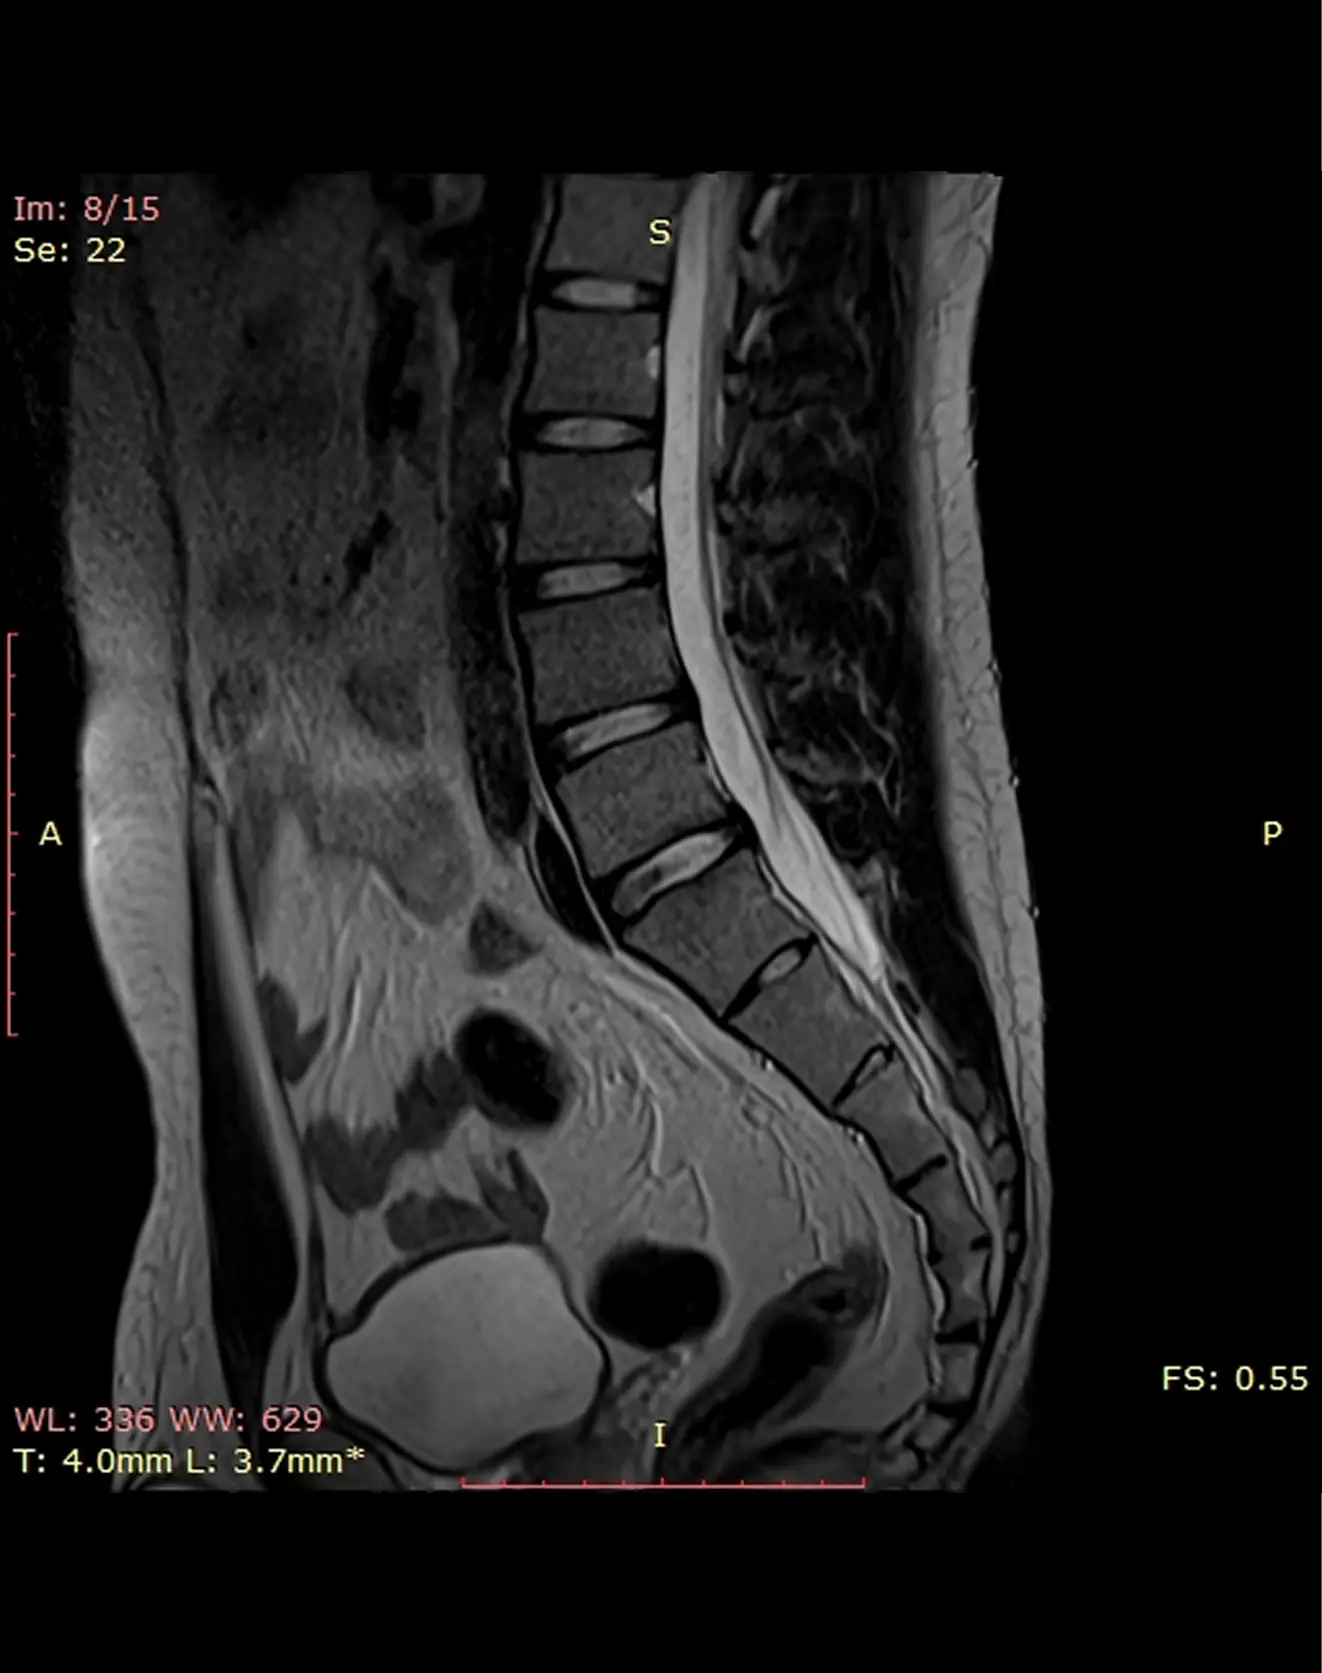

МРТ пояснично-крестцового отдела позвоночника

Визуализация позвонков поясничного и крестцового отделов позвоночника, межпозвонковых дисков, конуса спинного мозга, волокон конского хвоста, спинномозговых корешков, окружающих мягких тканей.